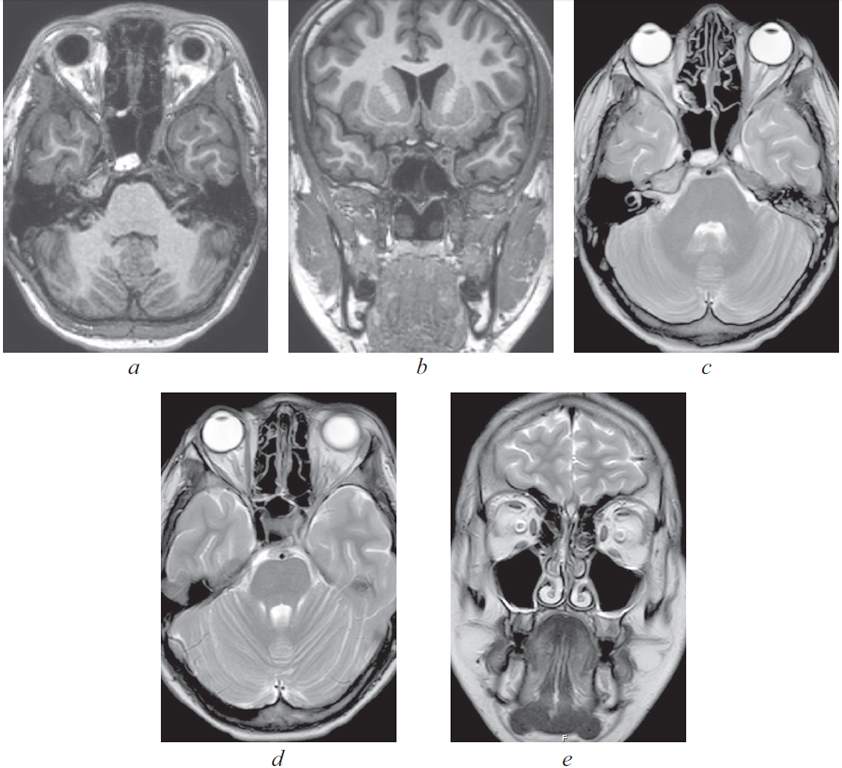

По результатам КТ ОНП от 08.11.2021: правосторонний сфеноидит с уровнем жидкости, левосторонний верхнечелюстной синусит с уровнем жидкости (рис. 4–6).

Рис. 4. Компьютерная томография околоносовых пазух и головного мозга от 08.11.2021: аксиальная проекция в режиме skull. Тотальное затенение правой половины пазухи клиновидной кости справа, уровень жидкости в левой верхнечелюстной пазухе

Fig. 4. Computed tomography of the paranasal sinuses and brain from 08.11.21: axial projection in skull mode. Total shading of the right half of the sphenoid sinus on the right, fluid level in the left maxillary sinus

Рис. 5. Магниторезонансная томография головы от 10.11.2021: правосторонний сфеноидит, тромбоз кавернозного синуса слева. Слева — коронарная проекция в режиме Т2. Тотальное затенение правой половины пазухи клиновидной кости, сужение кавернозного синуса слева; справа — аксиальная проекция в режиме Т2. Признаки тромбоза кавернозного синуса слева

Fig. 5. Magnetic resonance imaging of the head from 10.11.2021: right-sided sphenoiditis, thrombosis of the cavernous sinus on the left. Left: coronal projection in T2 mode. Total shading of the right half of the sphenoid sinus, narrowing of the cavernous sinus on the left; right: axial projection in T2 mode. Signs of thrombosis of the cavernous sinus on the left

Рис. 6. Магнитно-резонансная томограмма головного мозга. Признаки тромбоза кавернозного синуса. 1 — Венозный застой в ретробульбарной клетчатке; 2 — cужение просвета сифона внутренней сонной артерии слева; 3 — неоднородность структуры

Fig. 6. Signs of cavernous sinus thrombosis on magnetic resonance imaging of the brain. 1 — Venous congestion in the retrobulbar tissue; 2 — narrowing of the lumen of the siphon of the internal carotid artery on the left; 3 — structure heterogeneity